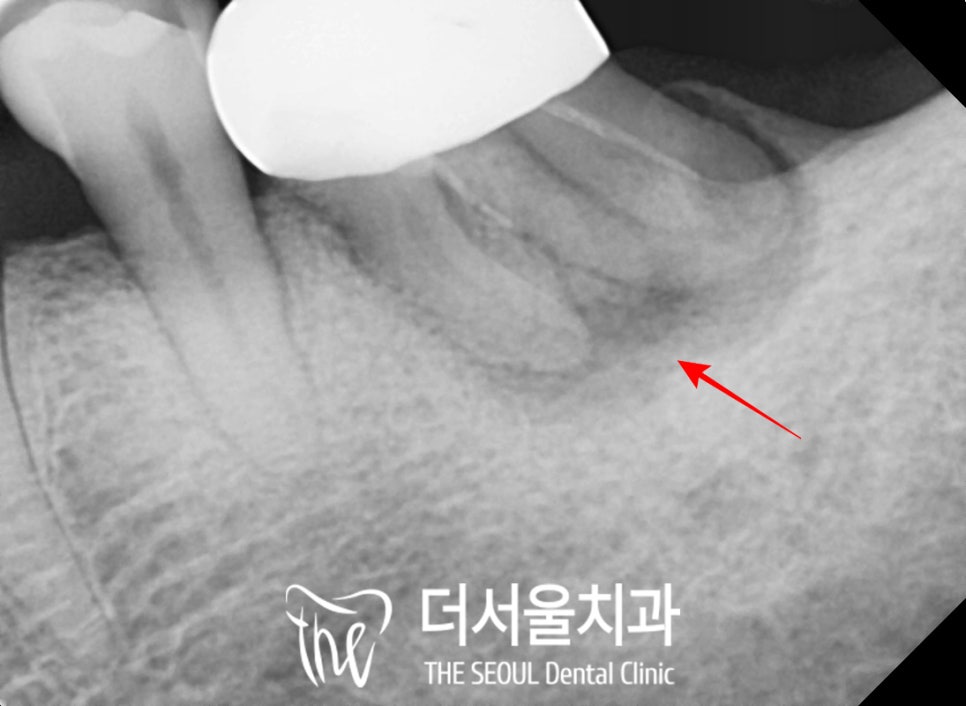

이 케이스에서도 뿌리 끝까지

진행된 치주 질환으로

발치를 판정했습니다.